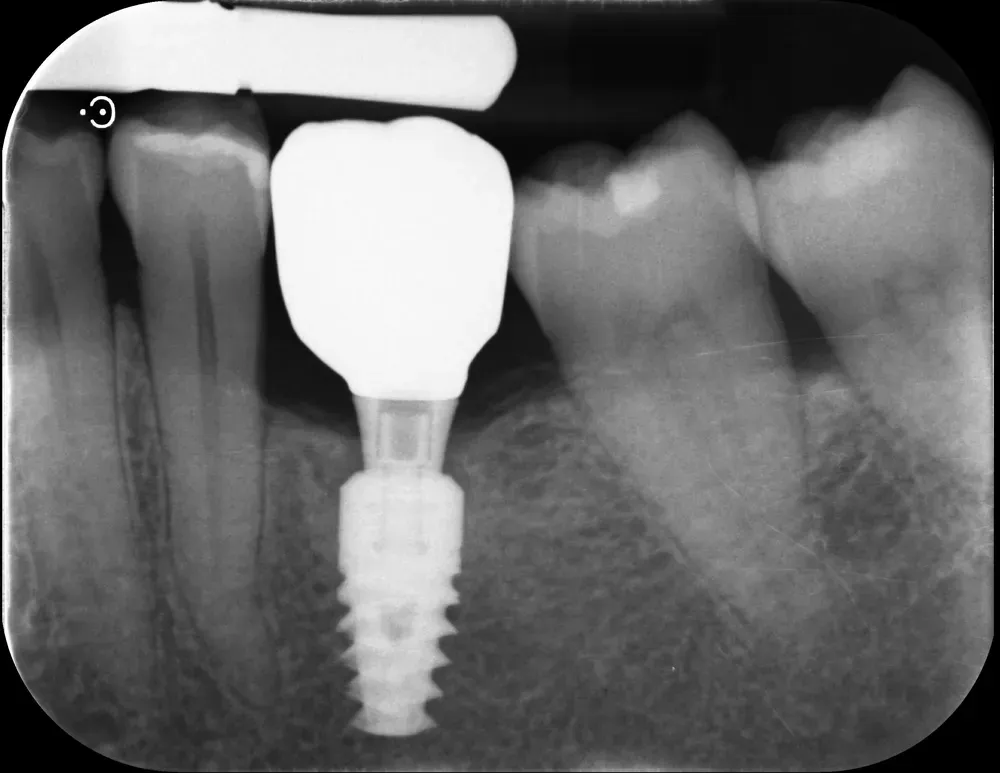

Gli impianti transmucosi devono essere posizionati transmucosi, soprattutto se hanno connessioni non particolarmente “sigillanti”. Usati in tal guisa, sono perfetti. Le immagini che seguono dimostrano che i transmucosi, se posizionati al giusto livello verticale, causano ZERO riassorbimento della cresta ossea.

La regola dei 4mm di Linkevičius ci viene in aiuto per stabilire la posizione verticale che protegge l’impianto dal riassorbimento osseo, sempre nel caso di connessioni affidabili dal punto di vista batteriologico. Nelle prossime immagini, dei monconi protesici relativamente lunghi su impianti a connessione conica, testimoniano l’ottimo risultato reale di questo concetto, con impianti perfettamente integrati e privi di infiltrazione infiammatoria, anche in condizioni ossee impegnative.

Per concludere il confronto tra le varie connessioni, l’immagine che segue è una radiografia con due impianti affiancati: un tissue-level ben posizionato fatto da un collega anni addietro e un impianto a connessione conica in posizione infracrestale con abutment della corretta lunghezza per il caso. Il secondo è un mio caso. È interessante notare come il cono dello spazio biologico sia identico. Se ben posizionati, tutti gli impianti funzionano egregiamente (l’impianto più vecchio inizia a soffrire un pochino, ma questa è un’altra storia).